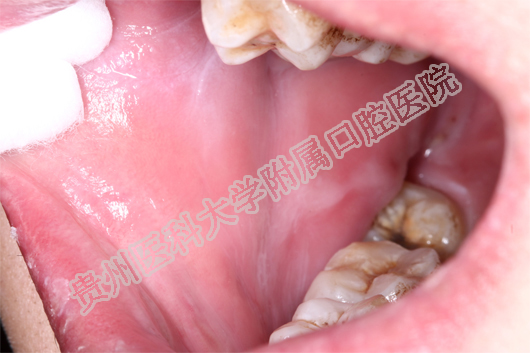

(患者治疗前后的舌部病损对比 上图:治疗前 下图:治疗1周后)

多见于嘴唇及颊部、舌头。开始时,口腔黏膜有烧灼感,明显充血发红、水肿,有时出现红斑、水疱,但疱很快破溃形成溃疡或糜烂。大面积的溃疡或糜烂会形成大量渗出物,形成假膜,疼痛非常明显,严重影响进食和说话。